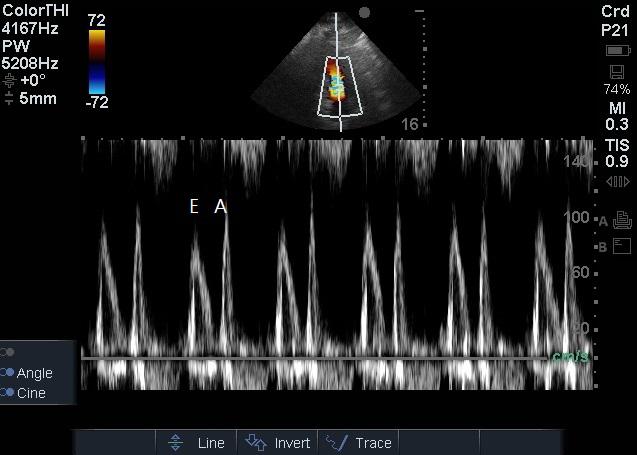

1.2 方法患者入院24 h内完成心脏超声检查。患者左侧卧位,以能显示心尖四腔心切面及五腔心切面为准,以美国Sonosite公司Edge超声诊断系统相控阵探头经心尖对患者二尖瓣、LVOT进行评估,彩色多普勒显示血流束,脉冲型频谱多普勒测量二尖瓣E峰流速及LVOT峰值流速(图 1~2),连续显示多个呼吸周期,选取呼吸周期内血流速变化规律波形,测量血流速最大值及最小值,重复以上过程,每个测量部位血流速共测量三组最大值及最小值,然后计算平均数。二尖瓣E峰流速呼吸变异度=(二尖瓣E峰流速最大值-二尖瓣E峰流速最小值)/[(二尖瓣E峰流速最大值+二尖瓣E峰流速最小值)/2],LVOT峰值流速呼吸变异度=(LVOT峰值流速最大值-LVOT峰值流速最小值)/[(LVOT峰值流速最大值+LVOT峰值流速最小值)/2][1]。

| 图 2 二尖瓣频谱多普勒检查 Figure 2 Mitral valve spectral Doppler examination |